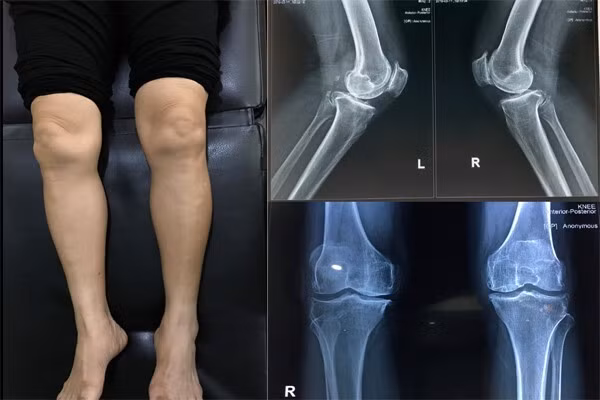

- Biến dạng khớp: Đầu gối sưng viêm có thể gây biến dạng lệch một bên hoặc lõm vào gây đau đớn.

Đau đầu gối nhẹ gây đau dai dẳng, âm ỉ, khó đi lại, cản trở sinh hoạt hàng ngày. Đau đầu gối nặng có thể gây đau đớn dữ dội, biến dạng khớp, không thể đi lại như bình thường.